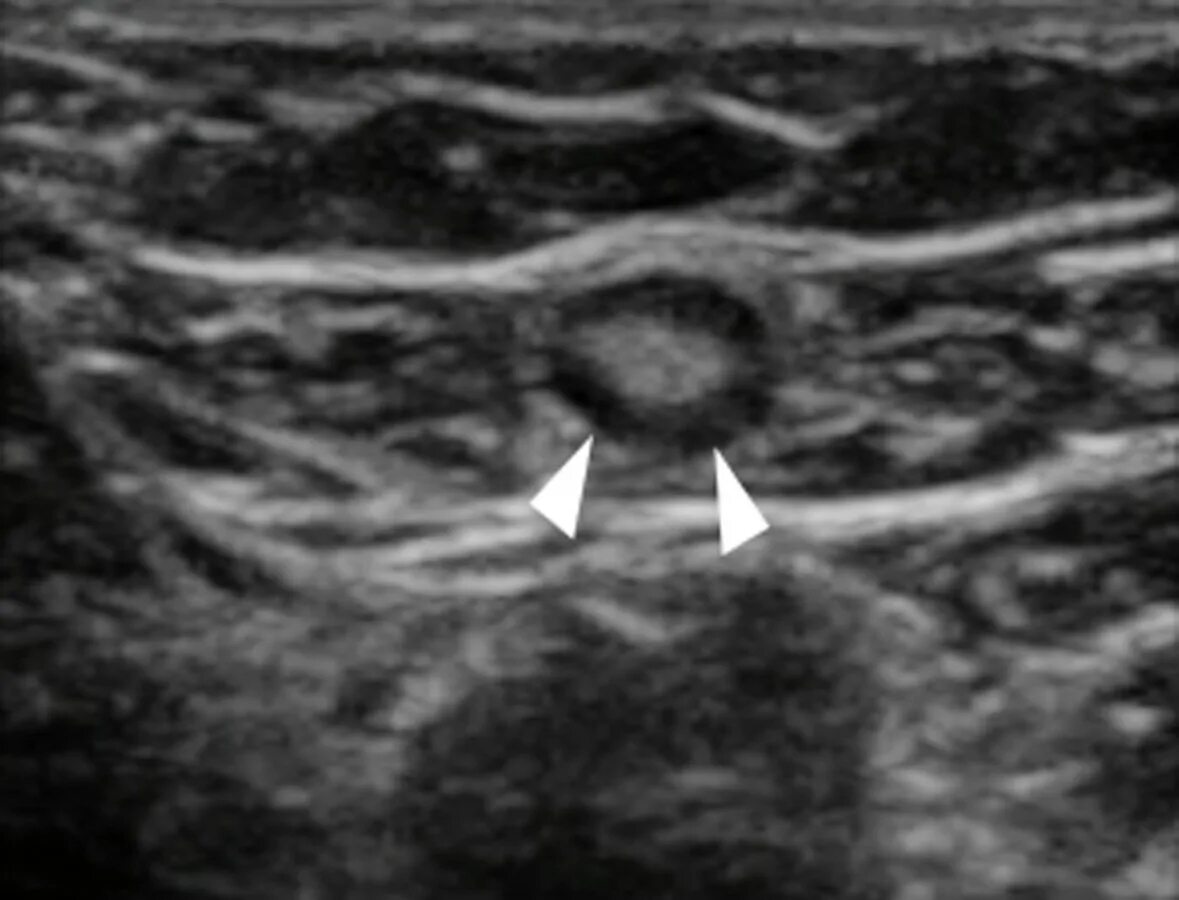

Метастазы в лимфоузлах молочной железы